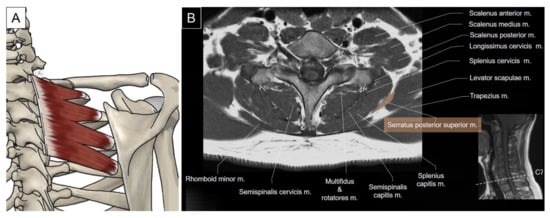

3. Intermediate Extrinsic Muscles

3.1. Serratus Posterior Superior/Inferior

3.1.1. Anatomy

3.1.2. Sonographic Scanning

3.1.3. Clinical Relevance

4.2. Iliocostalis/Longissimus/Splenius Cervicis

4.2.1. Anatomy

4.2.2. Sonographic Scanning

4.2.3. Clinical Relevance